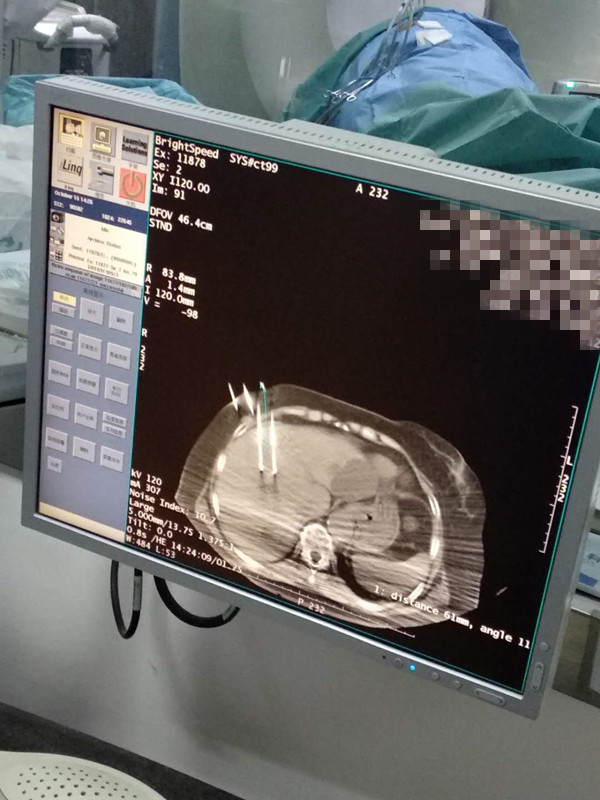

73岁患者肝部氩氦刀冷冻消融